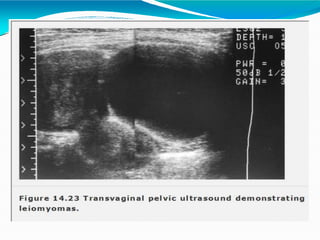

Imaging

Sonography is the most readily

available and least costly to

differentiate fibroids from other

pelvic pathology . It is reasonably

reliable forevaluation of uterus with

< 375 ccvolumeand 3-4 or fewer

fibroids.